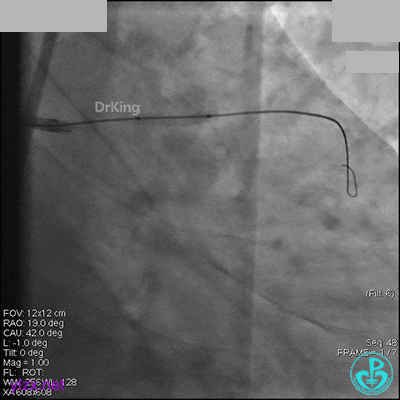

右冠脉中段充分扩张后欲植入3.5×38mm支架时,支架难以通过中远段扭曲处,且指引导管、导丝弹出飞扬。反复尝试导丝重新到达右冠脉远端时通过不顺利,局部造影剂滞留,远端血流接近3级。

右冠脉血流3级,患者无症状,终止手术。

术后患者无特殊不适。

1周后再次上台,右冠脉3级血流,3段局限性严重狭窄,内膜模糊,应该是上次操作夹层遗留下的血肿。